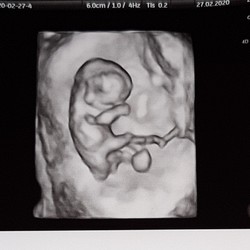

Ik ben nu 6 + 6 en ik heb ook 3 keer bloedverlies gehad in de 5e week. 1 keer was het echt rood en de andere keren lichtroze/bruin. Het stopte vrij snel en zette niet door. Paar keer ook in combinatie met menstruatieachtige krampen. Op de echo was gewoon een kloppend hartje te zien. Deze heb ik wel gekregen ivm het bloedverlies.